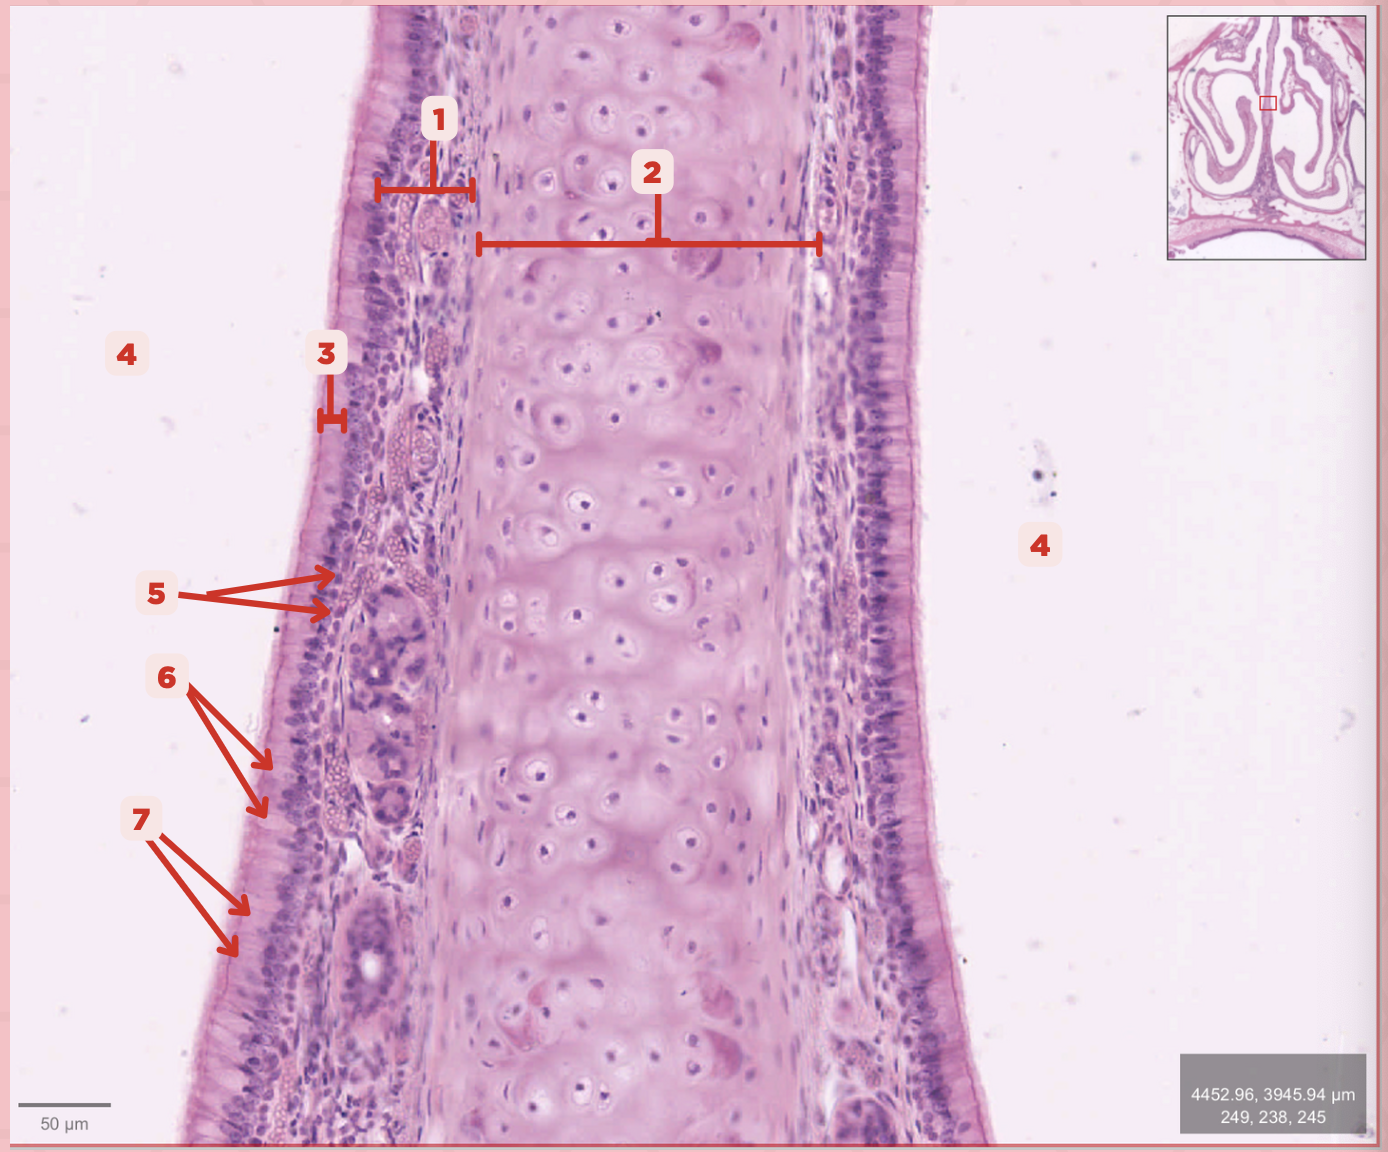

Identify the structure labeled as 1.

Hyaline Cartilage

Identify the structure labeled as 2.

Respiratory Epithelium

Identify the structure labeled as 3.

Nasal Cavity

Identify the structure labeled as 4.

Basal Cells

Identify the structure labeled as 5.

Goblet Cells

Identify the structure labeled as 6.

Ciliated Columnar Cells

Identify the structure labeled as 7.

Adipose tissue

What type of tissue is sometimes seen between the bony spicules?

Serous and Mucous Glands

What glands are present in the Lamina Propria?